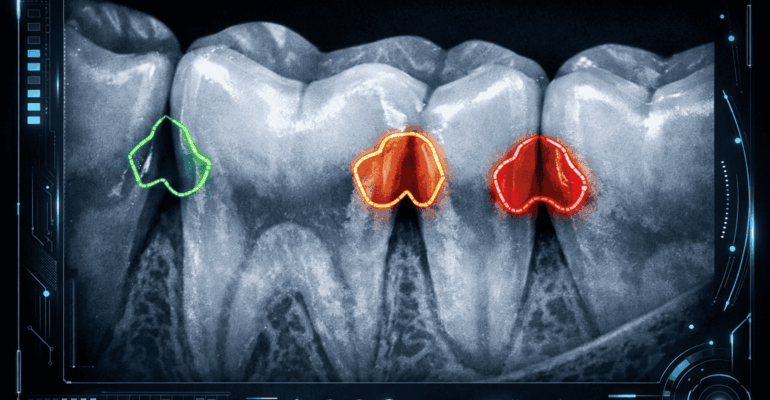

The image is instantly analyzed by AI software integrated into the practice’s imaging platform. The algorithm evaluates pixel density variations and compares them to vast datasets of confirmed cavity cases.

3. Highlighted Diagnostic Indicators

The software overlays color-coded markers on areas of concern, often assigning probability scores to indicate severity or likelihood of decay.

In 2026, AI integration is becoming a standard component of technologically advanced dental practices. Patients value visual transparency, and AI-generated overlays allow them to clearly see areas of concern on-screen.